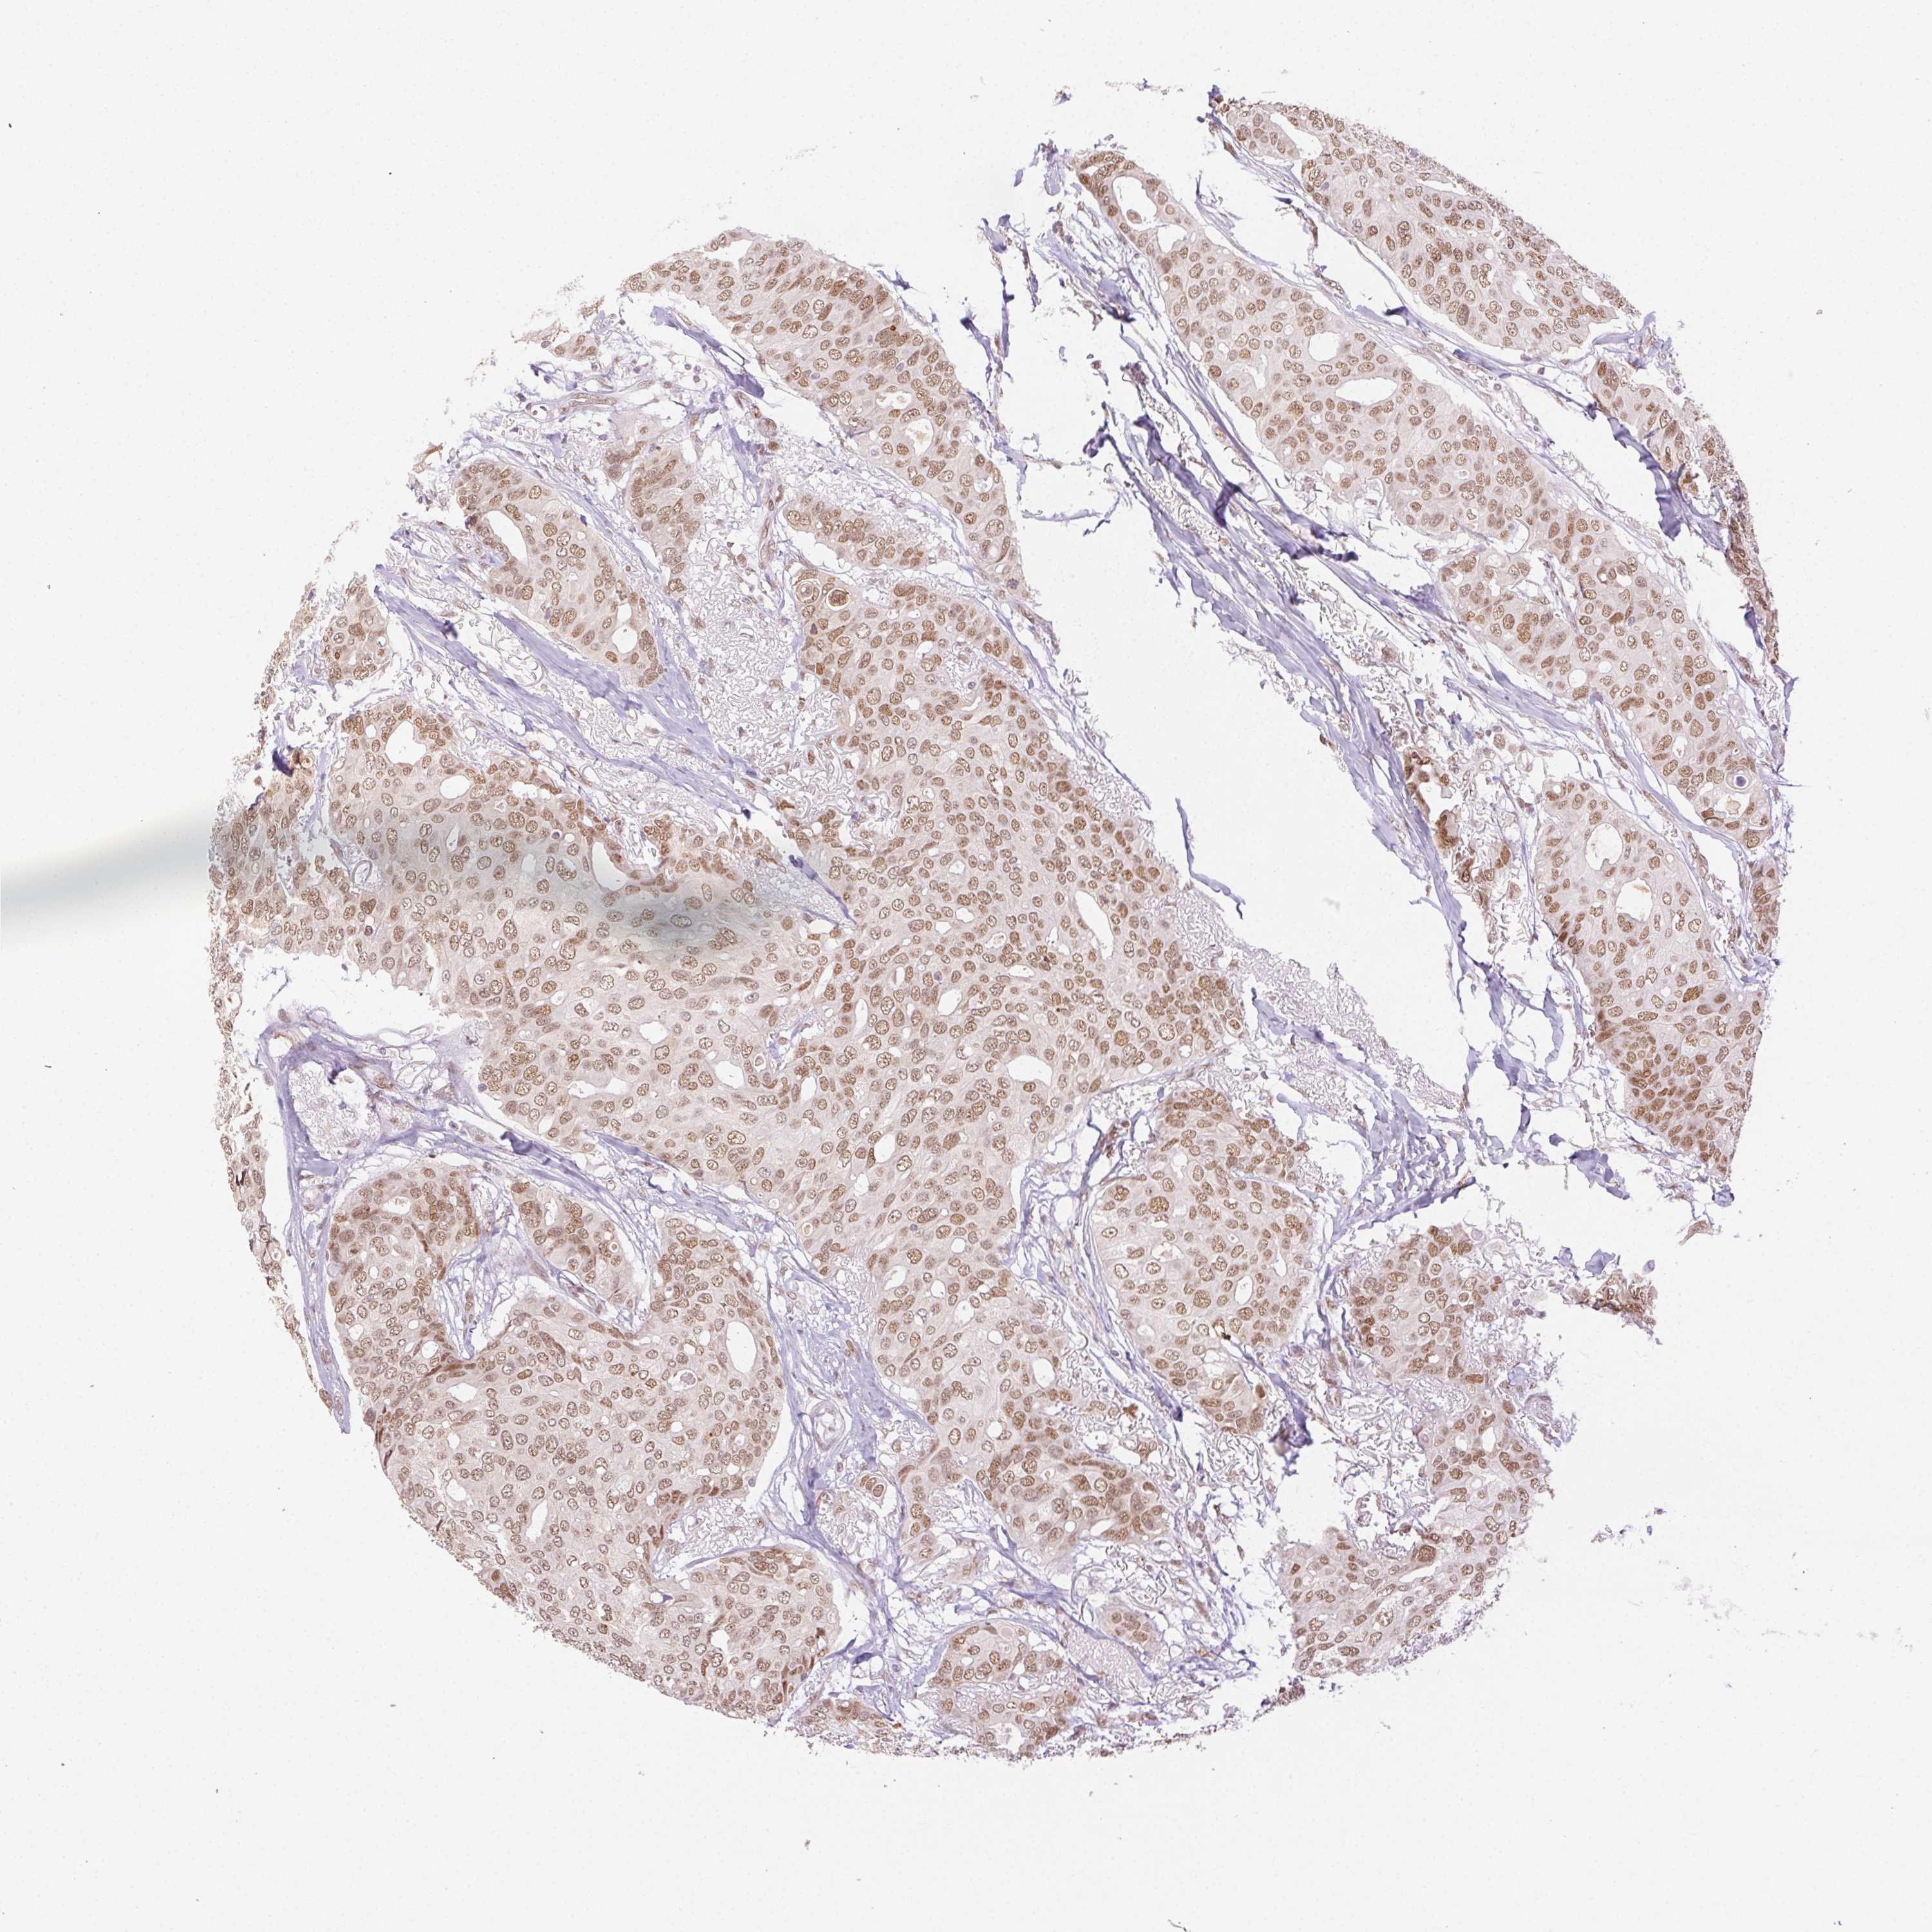

CANCER BREAST CANCER Show tissue menu

BRCA TCGA BRCA VALIDATION PROTEIN EXPRESSION

ANTIBODIES

AND

VALIDATION